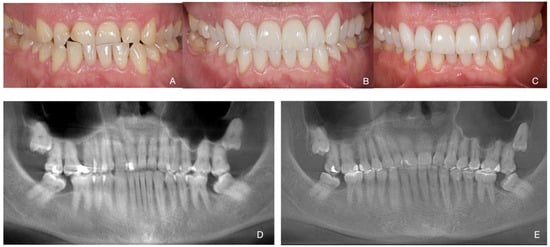

Total Rehabilitation Using Adhesive Dental Restorations in Patients with Severe Tooth Wear: A 5-Year Retrospective Case Series Study

3. Results